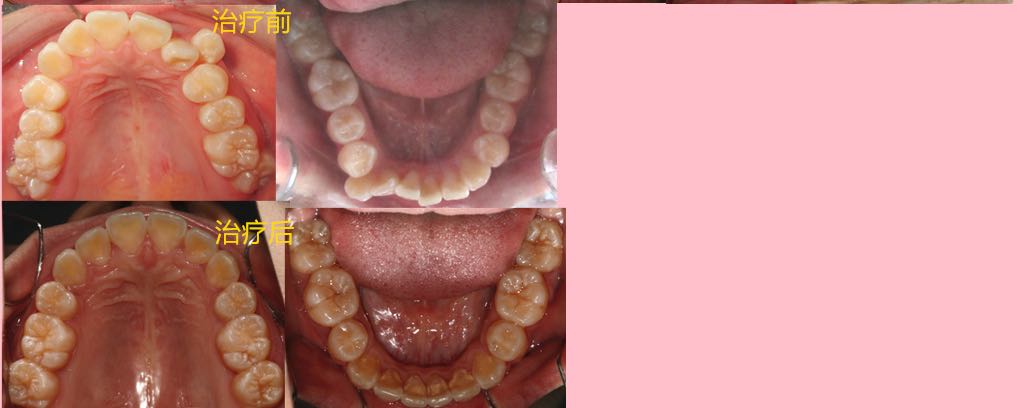

患者,女,14岁

患者神清气平,对答切题,生命体征平稳。面部基本对称,皮肤无红肿。口腔卫生良好,开口度及开口型正常,关节无弹响。双侧磨牙轻远中关系,右侧上颌尖牙位于牙弓之外,上颌重度拥挤,下颌中度拥挤,前牙深覆合I°,深覆盖II°,下颌中线居中与面中线一致,上颌中线右偏,面部左右不对称,右侧丰满,左侧欠丰满,上颌发育正常,下颌稍后缩,偏高角。

2、直丝弓拔牙矫治,拔牙部位为:14,24,34,44,上下颌中度支抗,排齐整平牙列,关闭拔牙间隙,调整中线及咬合关系。